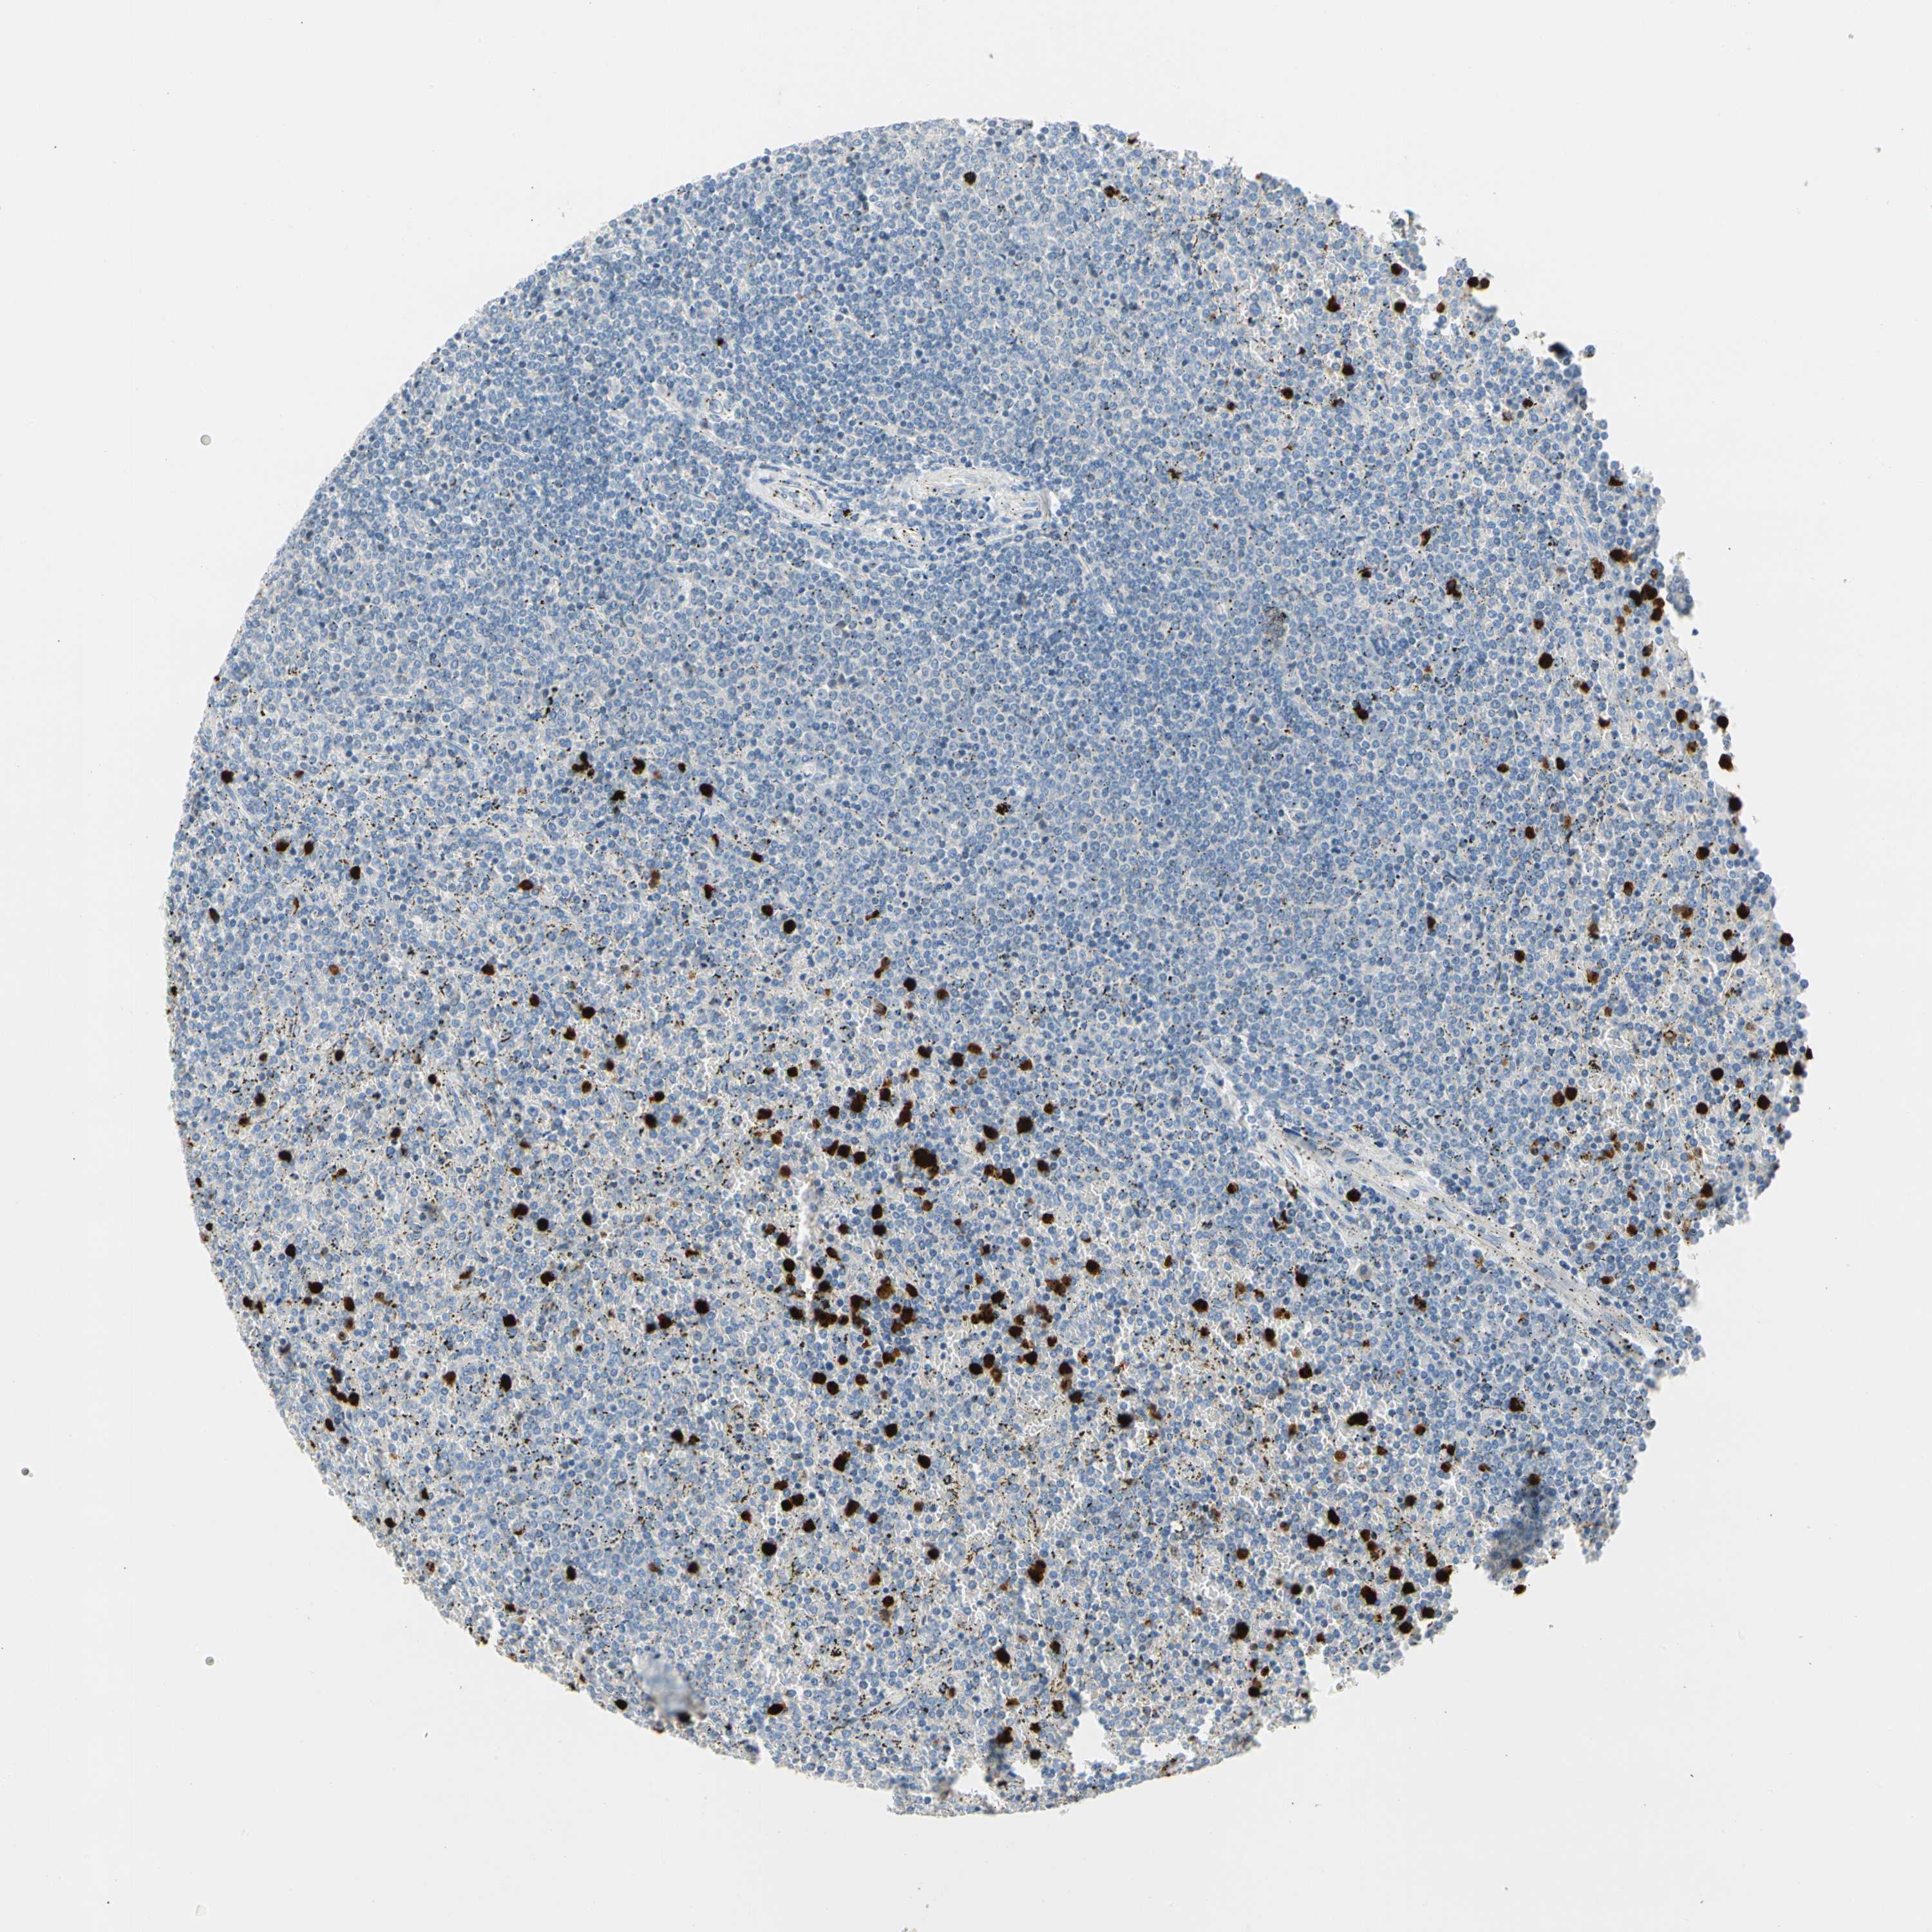

CANCER LYMPHOMA Show tissue menu

LYMPHOMA - Protein expressioni

A mouse-over function shows sample information and annotation data. Click on an image to view it in a full screen mode. Samples can be filtered based on level of antibody staining by selecting one or several of the following categories: high, medium, low and not detected. The assay and annotation is described here.

Antibody stainingi

Antibody staining in the annotated cell types in the current human tissue is reported as not detected, low, medium, or high, based on conventional immunohistochemistry profiling in selected tissues. This score is based on the combination of the staining intensity and fraction of stained cells.

Each image is clickable and will lead to virtual microscopy that enables deeper exploration of all samples and also displays staining intensity scores, fraction scores and subcellular localization as well as patient and tissue information for each sample.

Antibody HPA008052

Antibody CAB010277

Staining

High

Medium

Low

Not detected

Intensity

Strong

Moderate

Weak

Negative

Quantity

>75%

75%-25%

<25%

None

Location

Nuclear

Cytoplasmic/membranous

Cytoplasmic/membranous,nuclear

Hodgkin's disease, NOS

Malignant lymphoma, non-Hodgkin's type, Low grade

Malignant lymphoma, non-Hodgkin's type, High grade